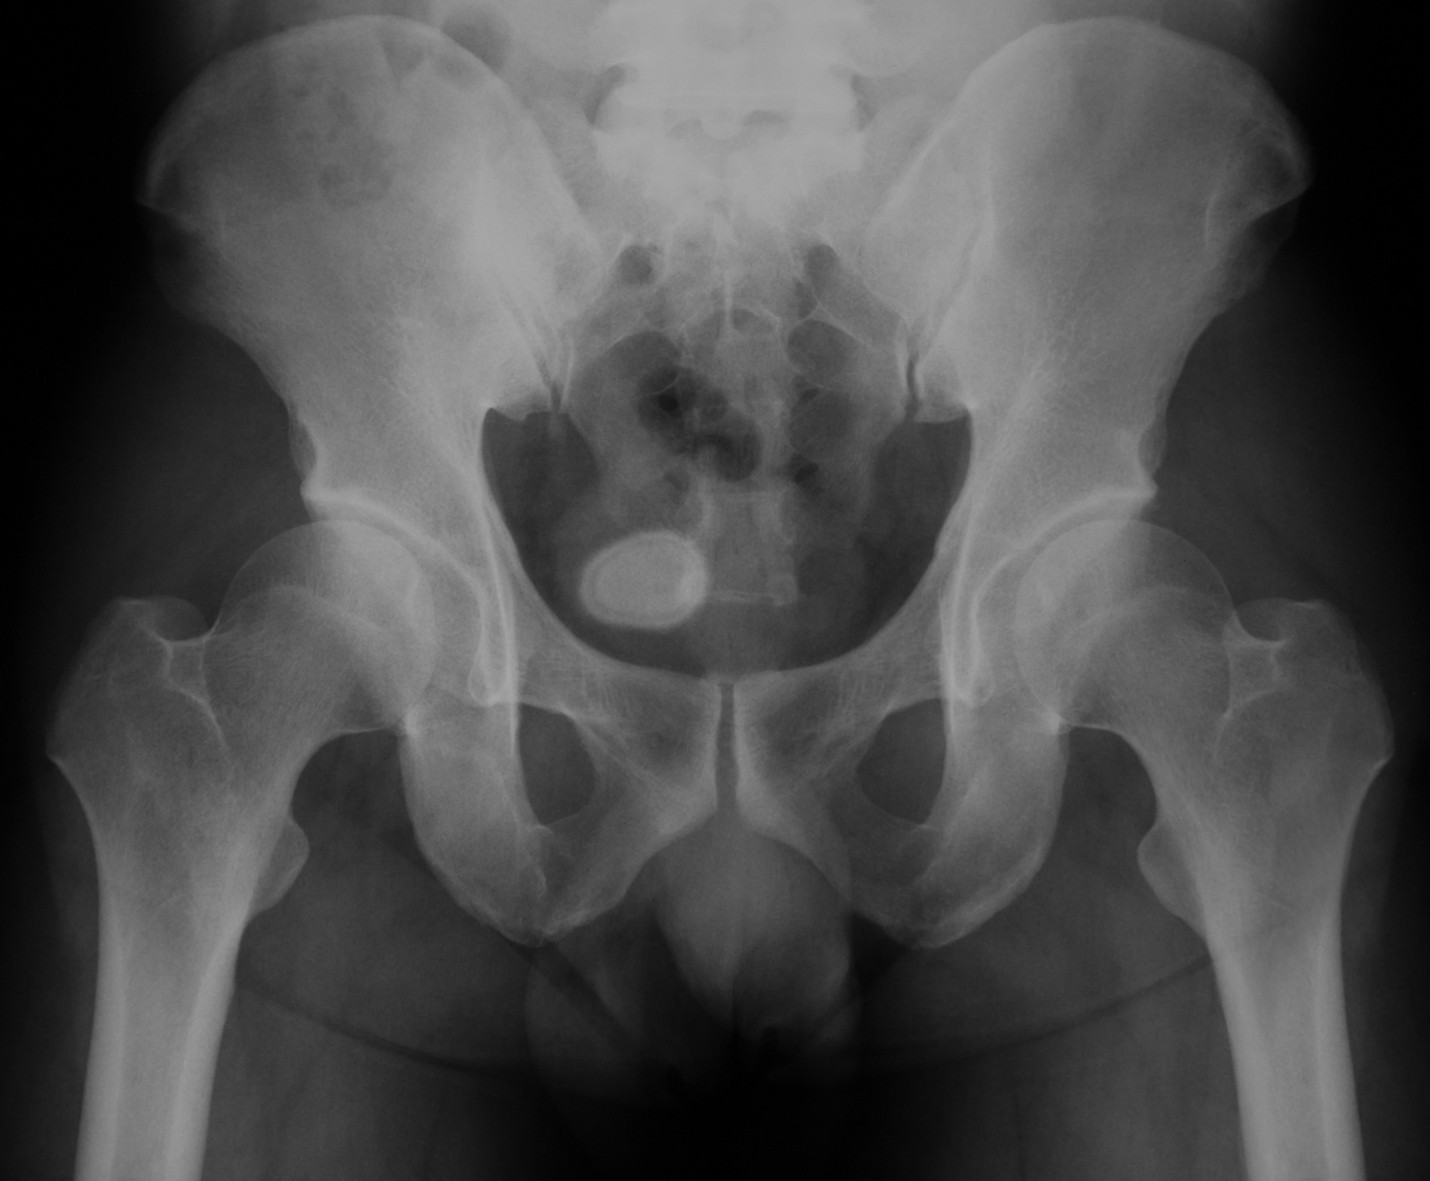

- Pelvic imaging (CT scan, X-ray, ultrasound)

- Urinary tract imaging (CT scan), which might include a special dye injected into your veins to highlights the stones